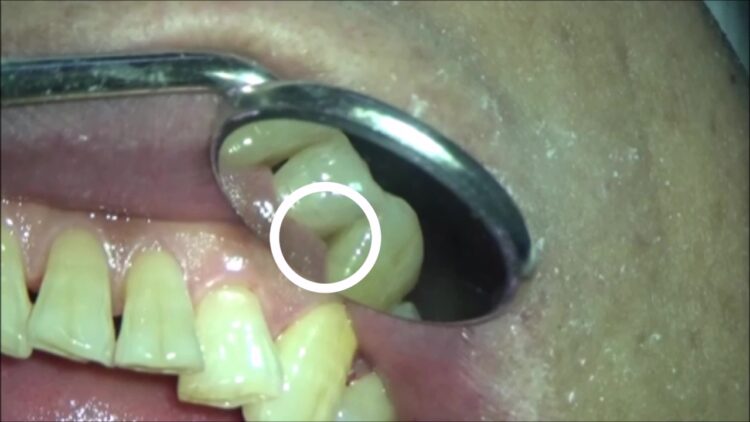

歯の間に青く染まってる所があります。

下写真○部

もう少し拡大してみましょう。

青い部分は3日以上前からくっ付いている虫歯菌の群れです。

因みに、3日間菌が付いたままになると、歯が溶け出します。

つまり、青いところは今までずっと歯が溶けていたことになります。

その積み重ねで、歯に穴が開いていくのです。

除去後

良く見ると歯に亀裂が入っているのが見えます。

ほんの少ししか付いていませんでしたが、あの細菌が亀裂から侵入し、歯の中で虫歯が進行するので要注意です。